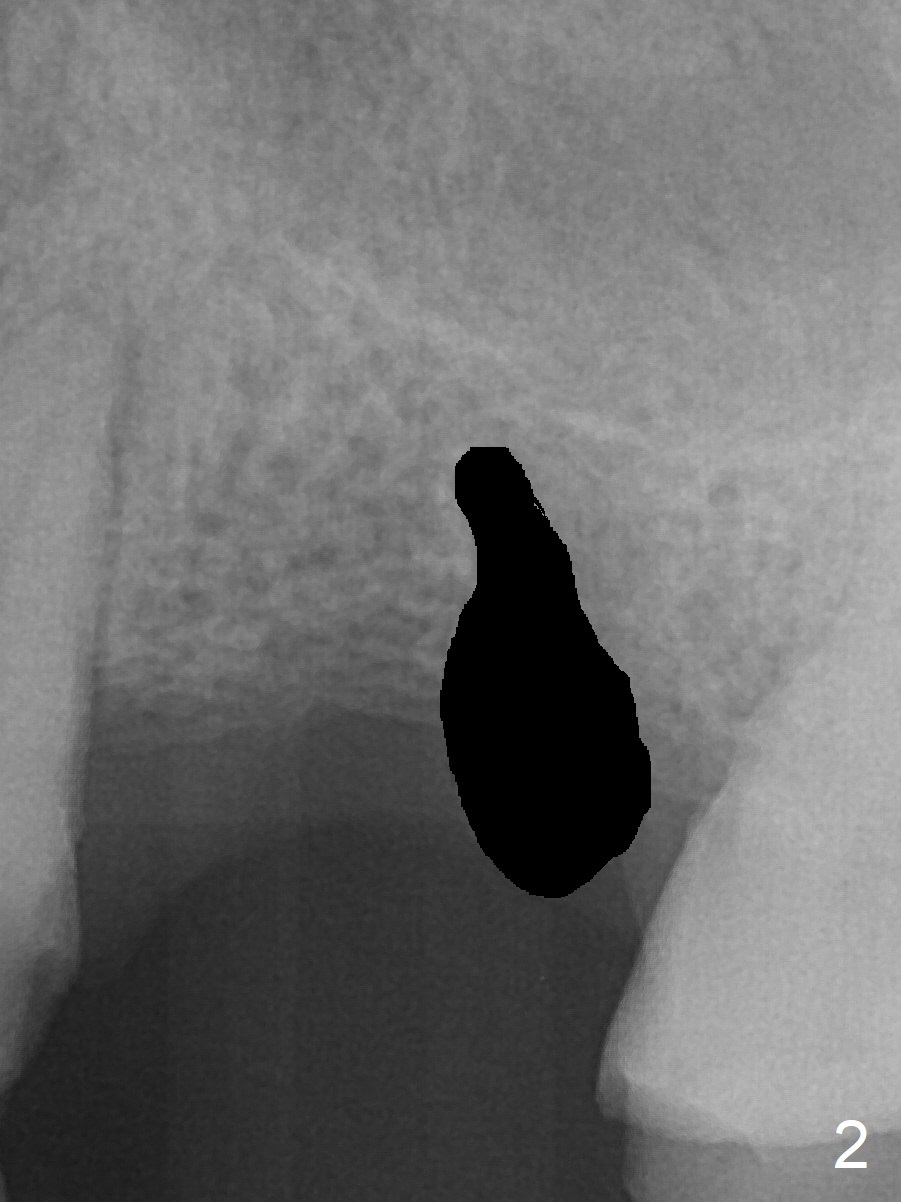

A 37-year-old man will return for #14 extraction and implant after RCT at #13 (Fig.1). After extraction (Fig.2), use Magic Expander (ME) along the long axis of the socket to initiate osteotomy shy of the sinus floor (Fig.3 (<9 mm gingival level)) and change the trajectory at the same time (Fig.4 white arrow). Take the 1st intraop PA when a small ME is stable. Gradually increase the depth for sinus lift as the diameter of MEs increases (Fig.5). Take preop photos to show the residual root and the alveolus (whether it is atrophic or not). Place bone graft (Fig.6 red circles) prior to dummy implant (green).